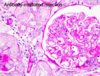

What are the typical histological features of T-cell mediated rejection?

- Lymphocytic interstitial infiltration

- Tubulitis - WBCs within the tubular epithelium

- Arteritis - WBCs within vascular wall

What are the main histological features of antibody-mediated transplant rejection?

- Presence of inflammatory cells within the capillaries of the graft (HALLMARK)

- Immunohistochemistry can show fixation of complement fragments on the endothelial cell surface